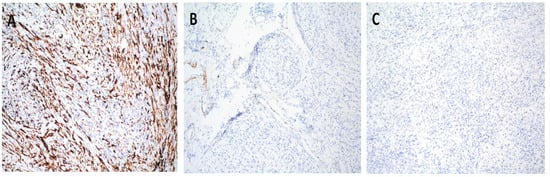

2. Case Report